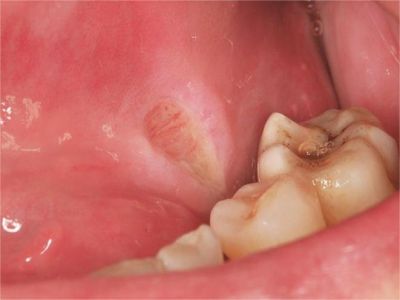

牙龈

糜烂 · 溃疡

创伤性溃疡牙龈上出现糜烂白块图

创伤性溃疡患者的下牙龈表面出现一块周围颜色潮红,形态呈圆形状,中间有白色糜烂面的溃疡,溃疡深者可以达到黏膜下层,痊愈后一般不易复发。